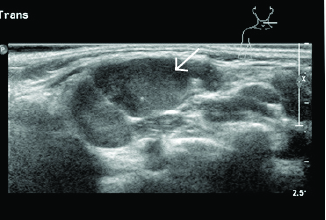

Typically, patients are febrile and have significant pain on neck movement, which can mimic meningismus. Soft tissue neck ultrasound or computed tomography (CT) may be helpful in defining the extent of abscess or surrounding cellulitis. (See Figures 1 and 2.) Empirical treatment of acute bacterial cervical lymphadenitis should provide adequate coverage for both Staphylococcus aureus, including community-associated methicillin-resistant S. aureus (CA-MRSA) if indicated by local microbiology patterns, and group A beta hemolytic Streptococcus.4 The initial drug of choice is amoxicillin/clavulanate potassium (Augmentin), although clindamycin is preferred where MRSA has high prevalence.4 Nodes with abscess formation may need incision and drainage if they show no improvement despite 48 hours of antibiotic treatment. Acute group A streptococcal (GAS) pharyngitis also may present with bilateral cervical lymphadenitis and is discussed later.

Figure 1. Enlarged Node in Cervical Lymphadenitis |

Image courtesy of Derya Caglar, MD. |

Figure 2. Enlarged Node in Cervical Lymphadenitis, Measuring |